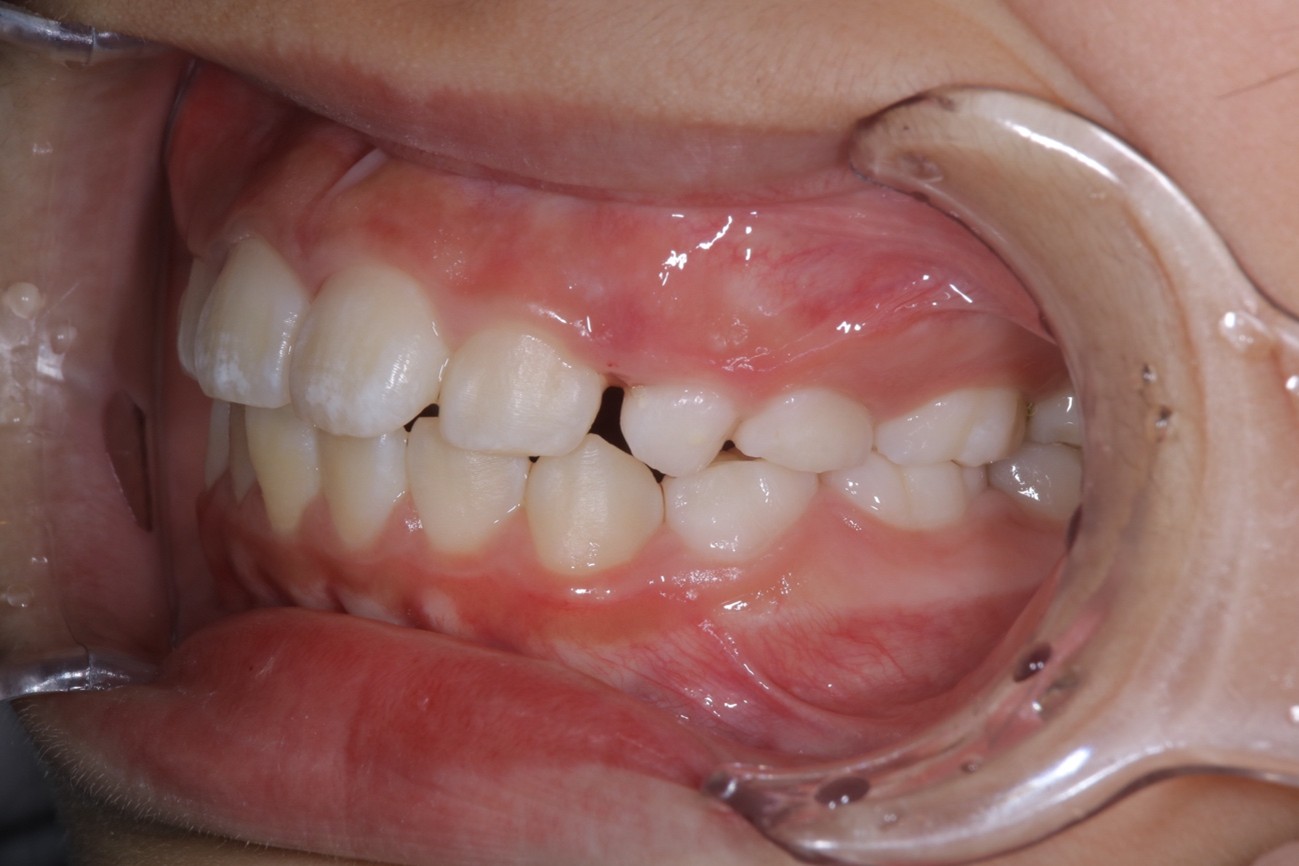

Before